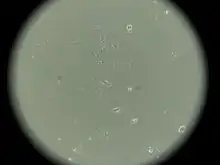

MCF-7 (Michigan Cancer Foundation-7) — эпителиоподобная клеточная линия, полученная из инвазивной аденокарциномы протоков молочной железы человека[1][2].

Линия была получена в 1973 году Гербертом Соулом и его сотрудниками в Институте рака Барбары Энн Карманос. До получения линии MCF-7 исследователи не могли получать линии клеток молочной железы, способной жить дольше нескольких месяцев. Сегодня эта линия является одной из наиболее распространенных линий клеток для исследований in vitro цитотоксичности противоопухолевых фармпрепаратов, молекулярной биологии рака[3], а также цитосовместимости различных биосовместимых материалов[2].